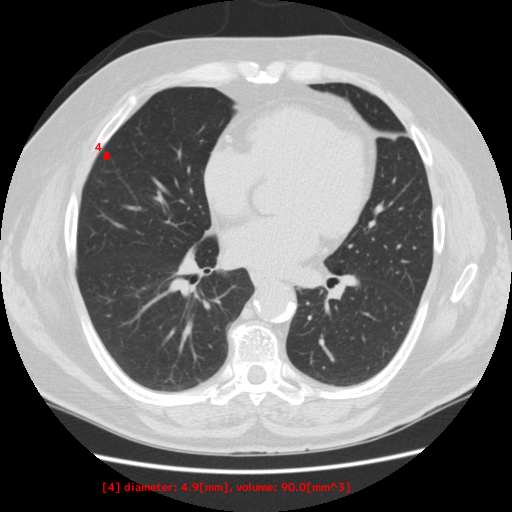

本製品は、胸部CT画像から肺野領域の組織について、使用者が設定した基準値に基づくCT値から「関心領域」を抽出し、その体積と最大径を自動計測します。計測した最大径が閾値以上となった場合には、画像上に色付けして表示します。この抽出・計測・表示機能は、医師が胸部CT画像を対象に読影診断を行う際に併用することで、肺野周辺組織とCT値が異なる肺結節等の視認性向上に寄与することが期待されます

【EIRL Chest CTによる表示例】

② 低線量CT

- 低線量CTについて

- 通常のCTに比べ、被検査者に与える被ばく量を軽減することが可能です。一方、撮影される画像は、通常のCTに比べて質が低下する傾向にあり、読影診断の難易度が高まると言われています。